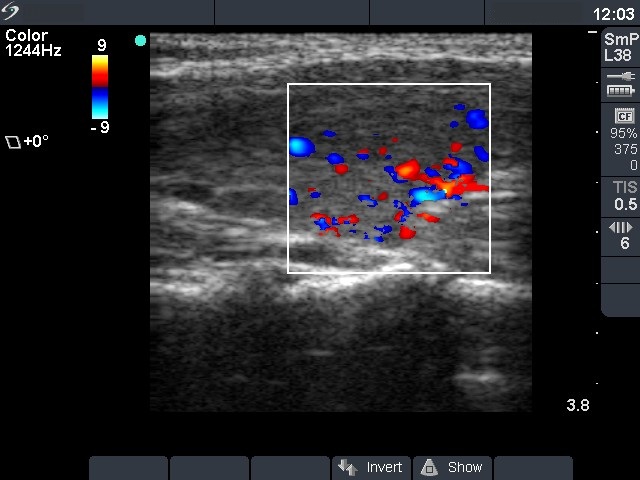

Follow-up investigation 12 months after first visit (ultrasonographic picture 6)

Patient on daily 10 mg methimazole therapy in euthyroid state

Left lobe, longitudinal scan, color Doppler mode. The vascularization is increased.